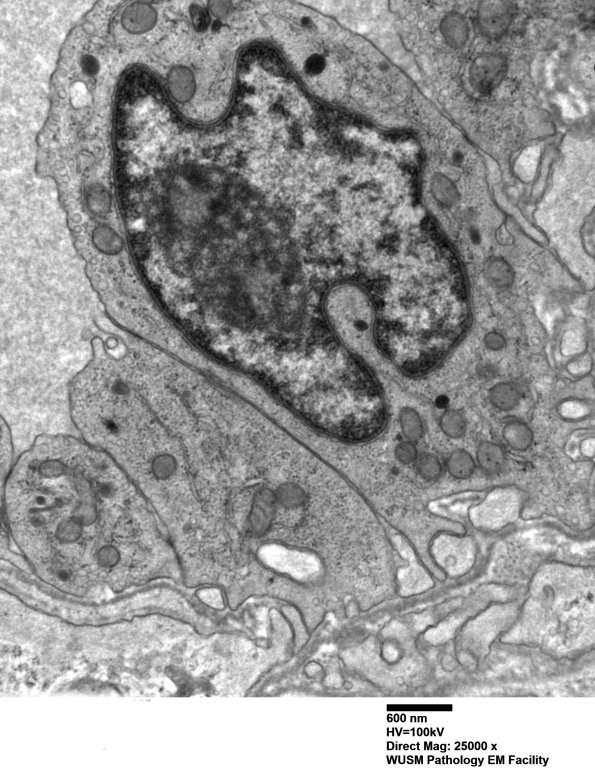

Washington University Experience | VASCULAR | Hypoxia-Ischemia, fetal-neonatal | White Matter | 15B4 (Case 15) HIEM EM 007 - Copy

15B4 (Case 15) HIEM EM 007 - Copy